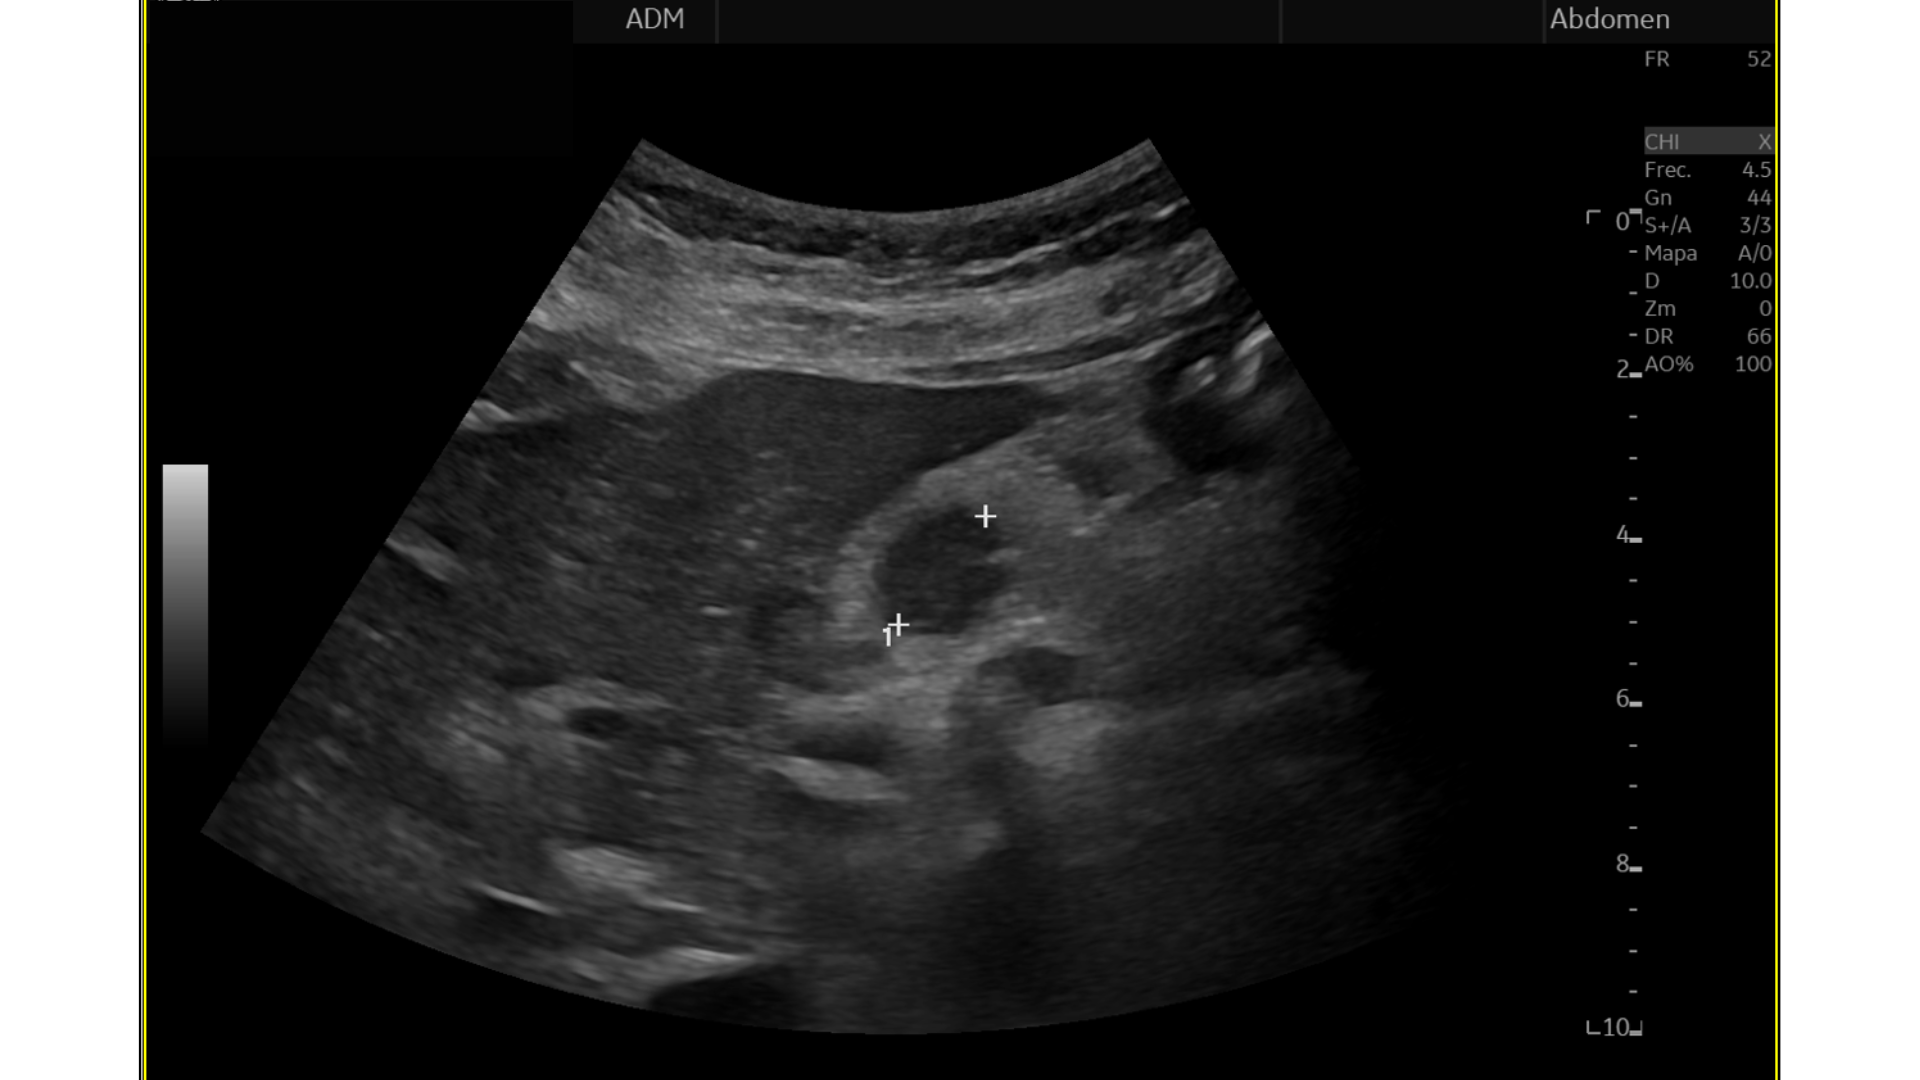

Eco Abdominal: Múltiples imágenes nodulares heterogéneas en ambos lóbulos hepáticos sugestivas de M1. Destaca imágen nodular, hipoecogénica en cabeza/cuerpo de páncreas de aprox. 17 mm, podría corresponderse con proceso neoformativo primario.